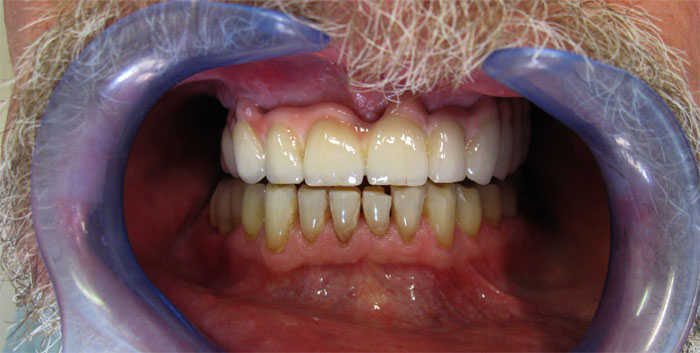

CAS N°1 Bridges et couronnes sur implant dentaire DIO et sur dents naturelles. Réhabilitation complète mâchoire supérieure, détartrage et blanchiment mâchoire inférieure.